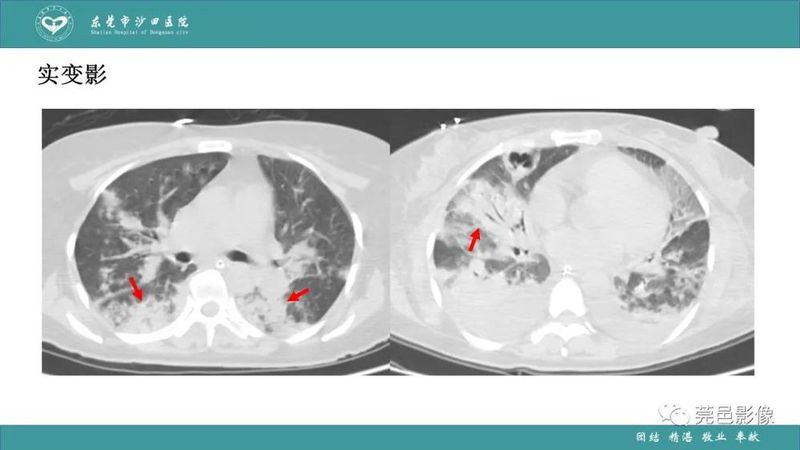

「肺炎克雷伯杆菌肺炎」影像学诊断+鉴别诊断